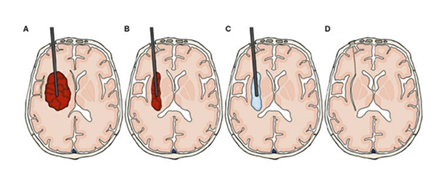

All patients received early intensive medication to lower the systolic blood pressure to ≤140 mmHg, according to established treatment regimens [17]. Patients in the surgical group were furthermore treated with the Artemis neuro evacuation device. These surgeries were performed by the same neurosurgeon at Odense University Hospital. The procedure was performed under general anaesthesia, and the patients were admitted to a neurointensive care unit after surgery. Figure 2 illustrates the endoscopic procedure step by step.

The procedure is performed by drilling a burr hole in the frontal area of the skull for insertion of the endoscope. As shown in figure 2A, the endoscope is then inserted in the brain via the burr hole under neuronavigation. When the endoscope has reached the posterior part of the haematoma, the surgeon starts a vibrating aspiration of the haematoma to relieve the pressure from the surrounding tissue (Figure 2B). When part of the haematoma has been aspirated and the initial pressure is relieved, the cavity is rinsed in sterile salt water under simultaneous aspiration (Figure 2C). The endoscope is retracted when the haematoma has been removed or when satisfactory volume reduction has been achieved and the water is aspirated (Figure 2D). Finally, the burr hole is covered with a small titanium net for cosmetic reasons.